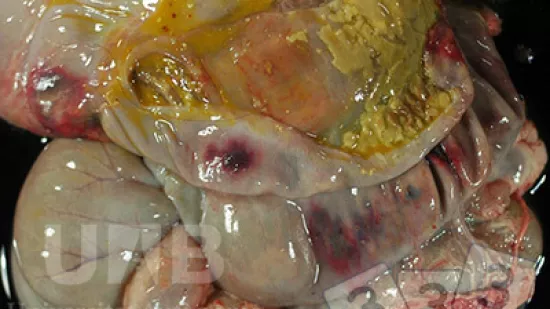

Was ist die Ursache für die vergrößerte Leber und Milz bei diesem adulten Zuchtschwein?